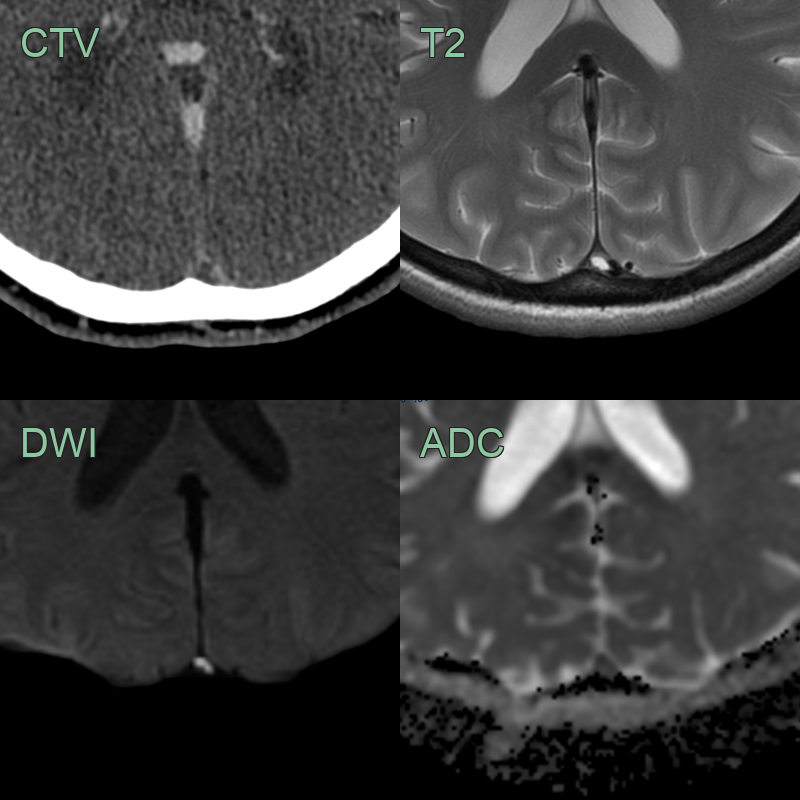

- 30-year-old patient presented with headache, confusion and expressive dysphasia.

- CT showed subtle hypodensity in the deep grey nuclei and hyperdensity within the straight sinus, vein of Galen, and internal cerebral veins. These structures were occluded on both the CTA and phase-contrast MRV.

- MRI showed hyperintensity and diffusion restriction in the deep grey nuclei. SWI showed congenstion of the deep venous system.

- 2 weeks later, a repeat MRI showed only very minimal hyperintensity in the thalami (where some microhaemorrhages had developed) indicating that the diffusion restriction was largely reversible although a few microhaemorrhages developed in the thalami.